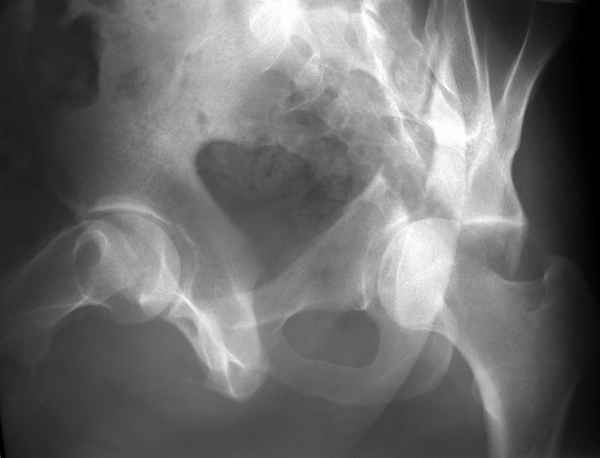

Разрушения оказались более обширные чем видно ра рентгенограмме. Только пять фрагментов с суставной поверхностью, два почти свободных. Послеоперационная картинка в цифре отсутствует, да она и не очень красивая. Удалось собрать суставную поверхность, много осколков без хряща на передне внутренней поверхности остались сами по себе, передние отделы теза синтезировал. Против обыкновения оставил больную на вытяжении.

Конечно изнутри таза массивная гиперпластическая мозоль - пришлось немного попотеть и интерпозиция по плоскости перелома. Хорошо был виден ствол нерва с внутренней стороны вырезки - сделали блокаду, как положено. После операции движения стопы в полном объеме чувствительных расстройств нет. Репозиция удалась - мы были в легкой эйфории - внесуставной доступ и т.д. Через сутки стопа повисла - грубых выпадений на ЭНМГ нет, но тем не менее ишемический неврит малоберцовой порции седалищного нерва - бич застарелых повреждений.

Ах если бы Русские люди не обманывали себя и больных, а направляли бы срочно в специализированные отделения, то можно было бы получить хороший результат куда меньшей кровью пациентов и сердечных ран хирургов. Посылаю еще два снимка. Привет ЛАФ.